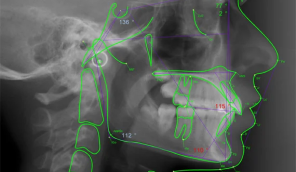

The Intended Audience for this course are dentists, dental hygienists, orthodontists, orthodontic assistants, dental specialists, and the students in these dental professions who plan to provide orthodontic care to patients. It is important to identify a patient’s underlying bone structure to diagnose a patient’s growth pattern and understand the relationships of the jaws, the teeth, and other structures. With this knowledge, the clinician will be able to properly treat the patient generating the most predictable and successful outcomes .

This full course trains the individual to be an expert in understanding cephalometrics and explains why the methods that are taught are the best that are known currently. The learner must pass all 8 smaller courses to develop expertise and earn the full 17 credits of the Cephalometric Imaging and Analysis Course. Individuals who have learned the important concepts from this course will be able to produce a cephalometric image, analyze it, and understand the significance of changes in cephalometric relationships over time.

- 40 Common Cephalometric Measures

- Digitizing and Analysis of a Cephalometric Image